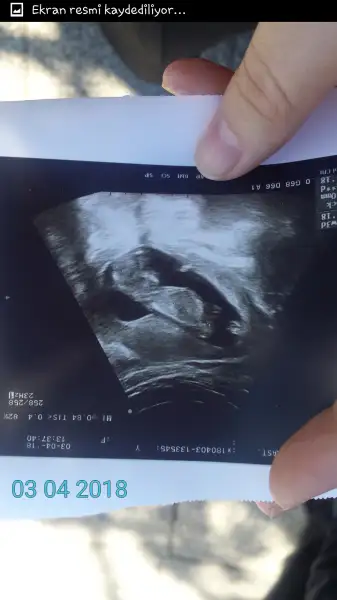

Erkek gibi geldi banaEki Görüntüle 2136532 Eki Görüntüle 2136532 yorum yaparmisiniz cinsiyet hakkinda :)

Hadi yaa .. herkez kiza benziyor diyor doktor söylemedi hic tahmin de yapmadi.. bende erkek hissediyorum .. bakalim hayirlisi sen anliyormusun bu istenErkek gibi geldi bana